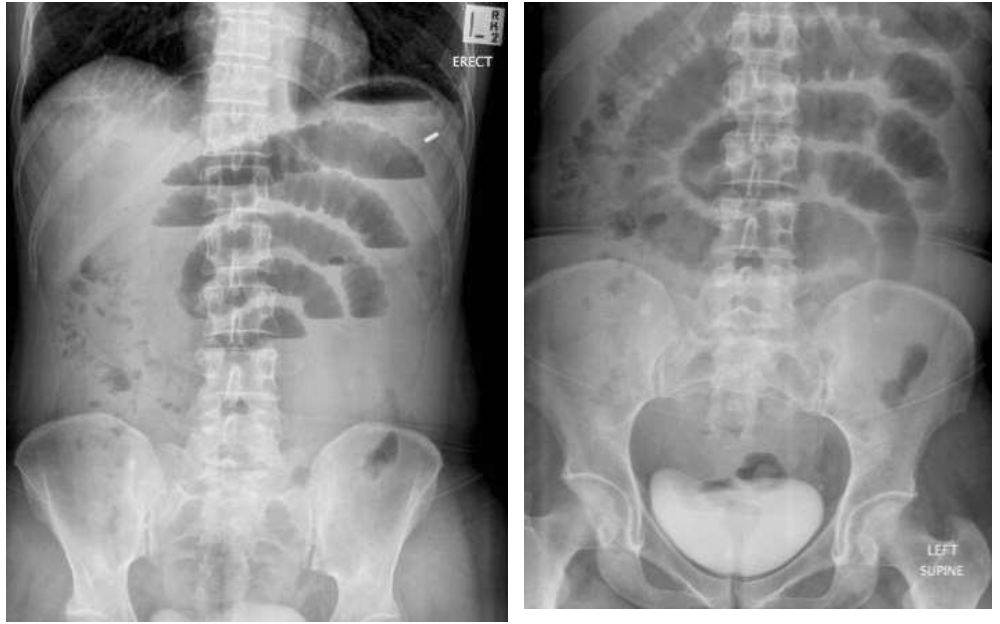

משמאל- ניתן לראות פלס אוויר- נוזל בריבה. כאשר לולאות המעי הדק רחבות מעל ל3 מ״מ זה מעיד על חסימה.

מימין- הצילום נעשה בשכיבה (שייך לאותו חולה), רואים את האוויר, אי אפשר לראות פלסים כי זה בשכיבה.